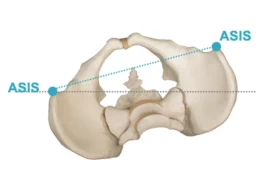

يؤثر بشكل مباشر على توازن الحوض

اختلاف واضح في مستوى الحوض

ميل واضح في الحوض

تقييم مستوى الحوض والكتفين